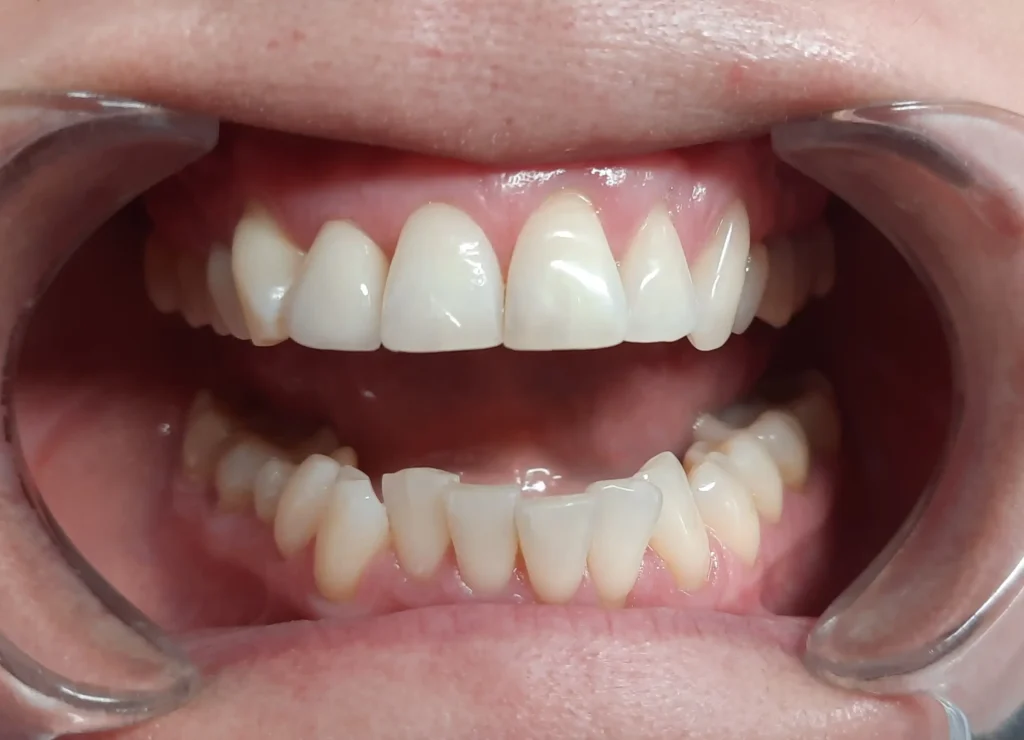

Pacjentka zgłosiła się do naszej kliniki z licznymi brakami w uzębieniu, które nie tylko wpływały na estetykę jej uśmiechu, ale także utrudniały codzienne funkcjonowanie. Nieprawidłowości w rozkładzie sił żucia, trudności w artykulacji oraz dyskomfort psychiczny związany z niepełnym uzębieniem stanowiły istotny problem, wymagający interdyscyplinarnego podejścia terapeutycznego.

Proces leczenia rozpoczęliśmy od kompleksowej diagnostyki oraz wdrożenia leczenia zachowawczego, którego celem było przygotowanie zębów do dalszej odbudowy protetycznej. W przypadku zębów niemożliwych do uratowania podjęliśmy decyzję o ich ekstrakcji, co pozwoliło na eliminację potencjalnych źródeł stanu zapalnego i przywrócenie prawidłowych warunków okluzyjnych.

Kluczowym etapem terapii była rekonstrukcja braków zębowych z wykorzystaniem mostów protetycznych. W odcinku przednim zastosowaliśmy estetyczne mosty pełnoceramiczne na podbudowie z tlenku cyrkonu, które dzięki swoim właściwościom optycznym doskonale imitują naturalną translucencję szkliwa i harmonijnie komponują się z fizjonomią twarzy pacjentki. W odcinkach bocznych, ze względu na większe obciążenia mechaniczne związane z żuciem, zdecydowaliśmy się na zastosowanie mostów na podbudowie metalowej, gwarantujących trwałość i wysoką odporność na siły działające w odcinku bocznym.

Efekt leczenia to pełny, funkcjonalny i estetyczny uśmiech, który nie tylko przywrócił pacjentce komfort w codziennym funkcjonowaniu, ale również znacząco wpłynął na jej pewność siebie i jakość życia. Dzięki indywidualnie dopasowanemu planowi leczenia oraz zastosowaniu nowoczesnych technologii protetycznych udało się osiągnąć rezultat spełniający zarówno wymagania estetyczne, jak i biomechaniczne.